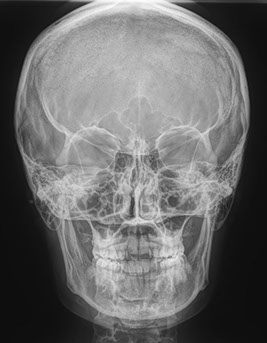

cephalometric

Cephalometric images (cephs) are used primarily in orthodontic diagnosis to measure the facial bones, including the jaws, to help determine treatment. Lateral cephs also show possible airway obstruction. PA cephs are used primarily to assess symmetry.